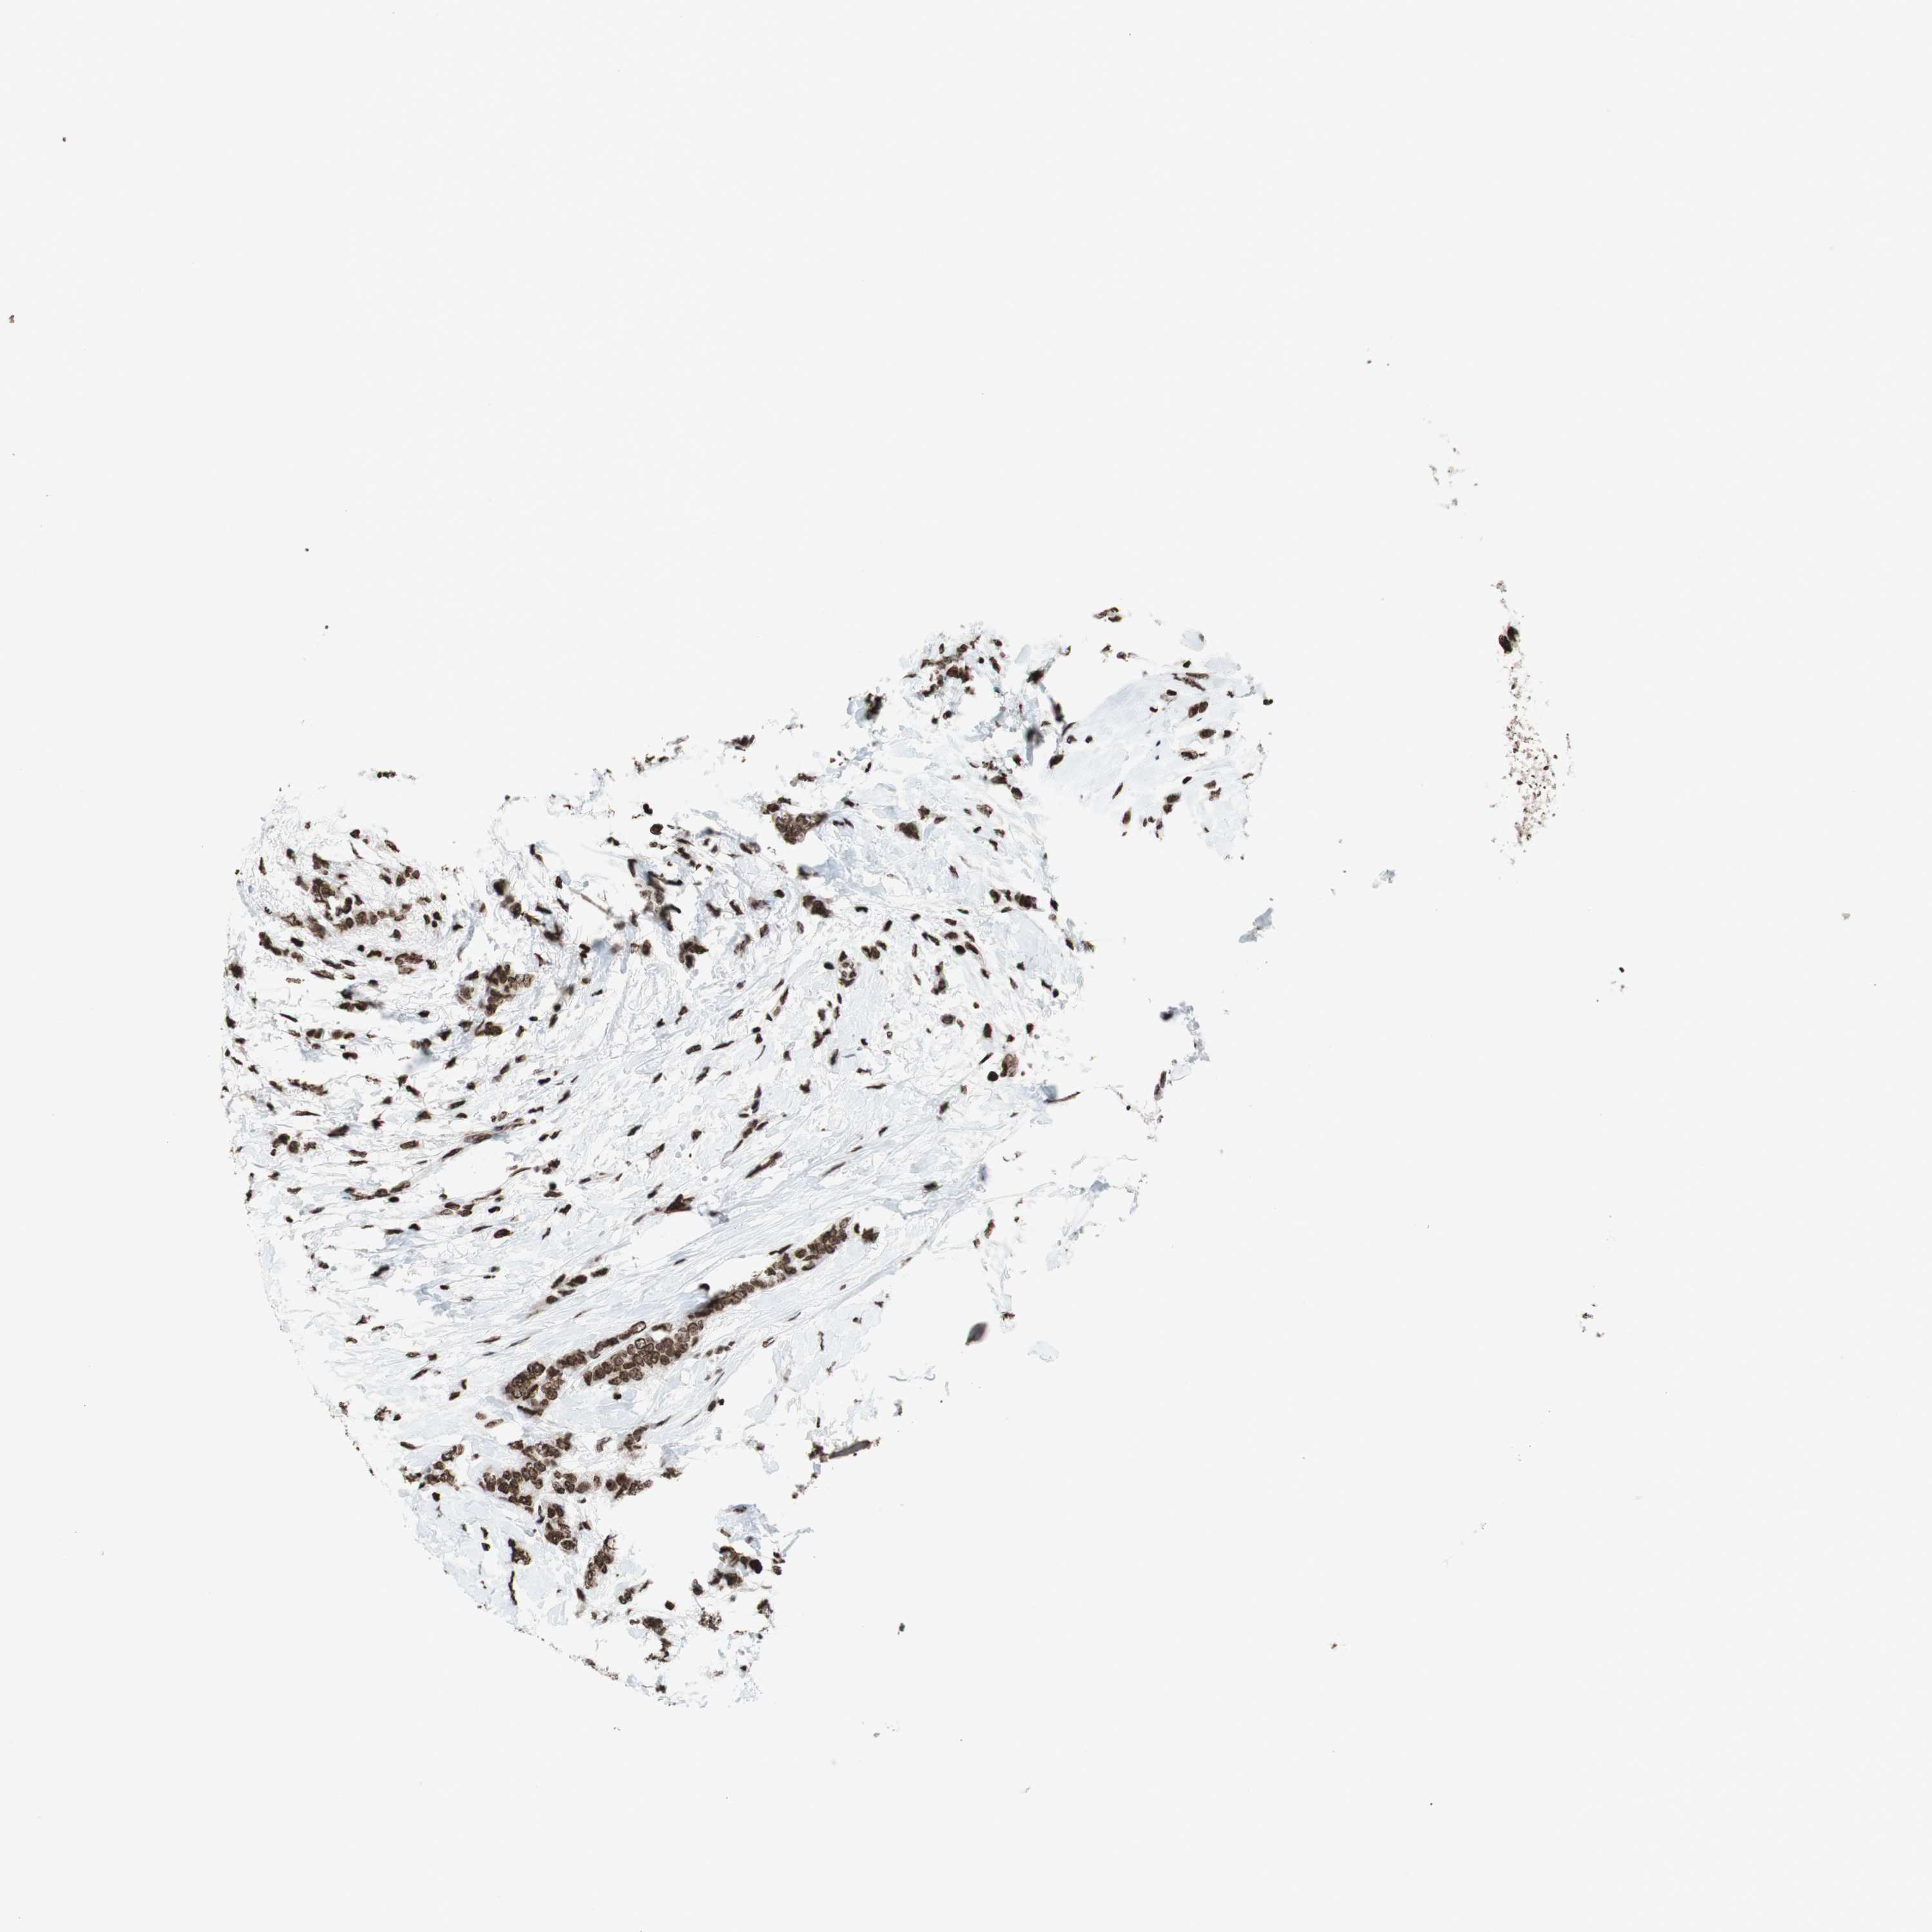

BRCA TCGA BRCA VALIDATION PROTEIN EXPRESSION